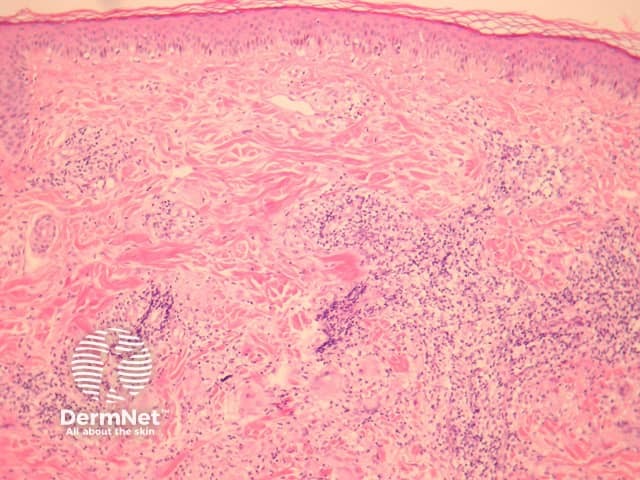

Sections show a granulomatous and lymphocytic infiltrate involving the dermis (figures 1, 3). The giant cells often contain asteroid bodies (figure 2, arrows). There is an associated infiltrate containing histiocytes, lymphocytes and some plasma cells (figures 1, 2).

Figure 1